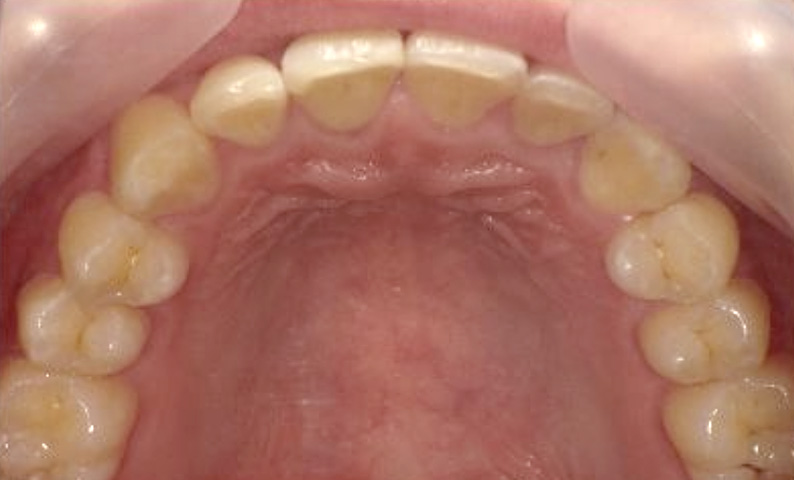

症例_001 上下顎の部分矯正

治療期間:10ヶ月金額:51万円+税女性八重歯前歯のガタガタ

| Before | After |

|---|---|

|